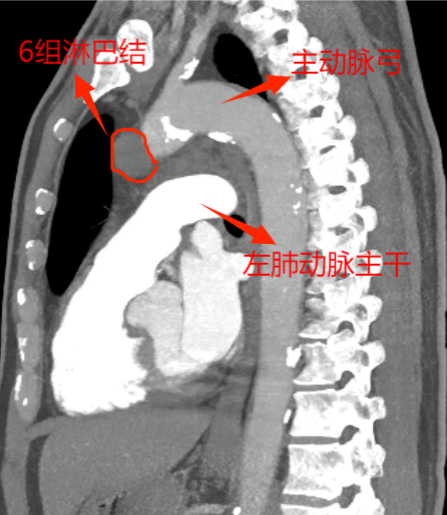

這下讓外科手術(shù)團隊為難了,因為兩組淋巴結(jié)臨近主動脈及左肺動脈2處大血管,位置深,即使CT引導下穿刺活檢,僅毫厘之差,仍大概率會出現(xiàn)大出血、氣胸,甚至危及生命,需緊急開胸,不活檢。由于轉(zhuǎn)移瘤性質(zhì)難定,影響后續(xù)方案的制定,家屬也很焦慮。

為實現(xiàn)更微創(chuàng),手術(shù)采取了單孔胸腔鏡技術(shù)。此次手術(shù),慶幸的是左肺與胸腔粘連不嚴重,但5、6組轉(zhuǎn)移淋巴結(jié)又硬又緊,與周圍組織界限欠清,尤其是5組淋巴結(jié),深埋進主動脈弓與左肺動脈根部,左主支氣管間,旁邊還有重要的迷走神經(jīng)及喉返神經(jīng)。血管損傷可能導致大量出血,神經(jīng)損傷可能造成聲音嘶啞、飲水嗆咳等并發(fā)癥。